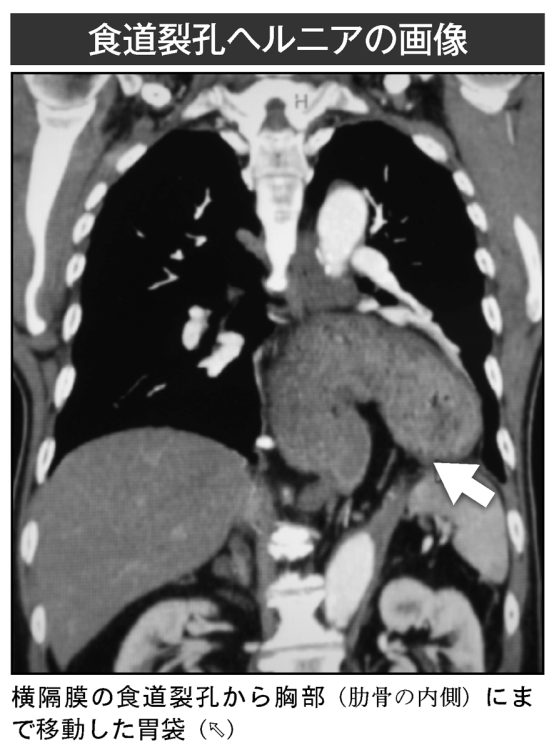

食道裂孔ヘルニアの画像